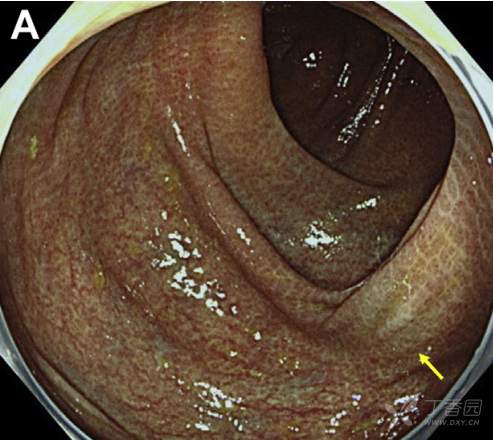

肠镜检查可见全结肠粘膜呈棕黑色,由盲肠至降结肠另可见多发淡青铜色区(图A)。病理所见如图B,图C为局部放大所见。